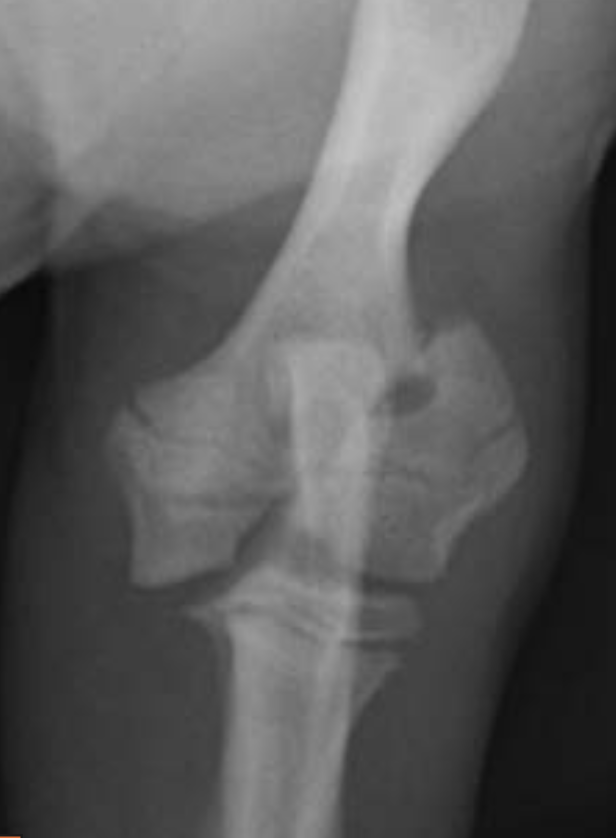

3.5m Yorkie

lateral humeral condylar fracture - see its caudal displacement, superimposed over the cranial ulna.